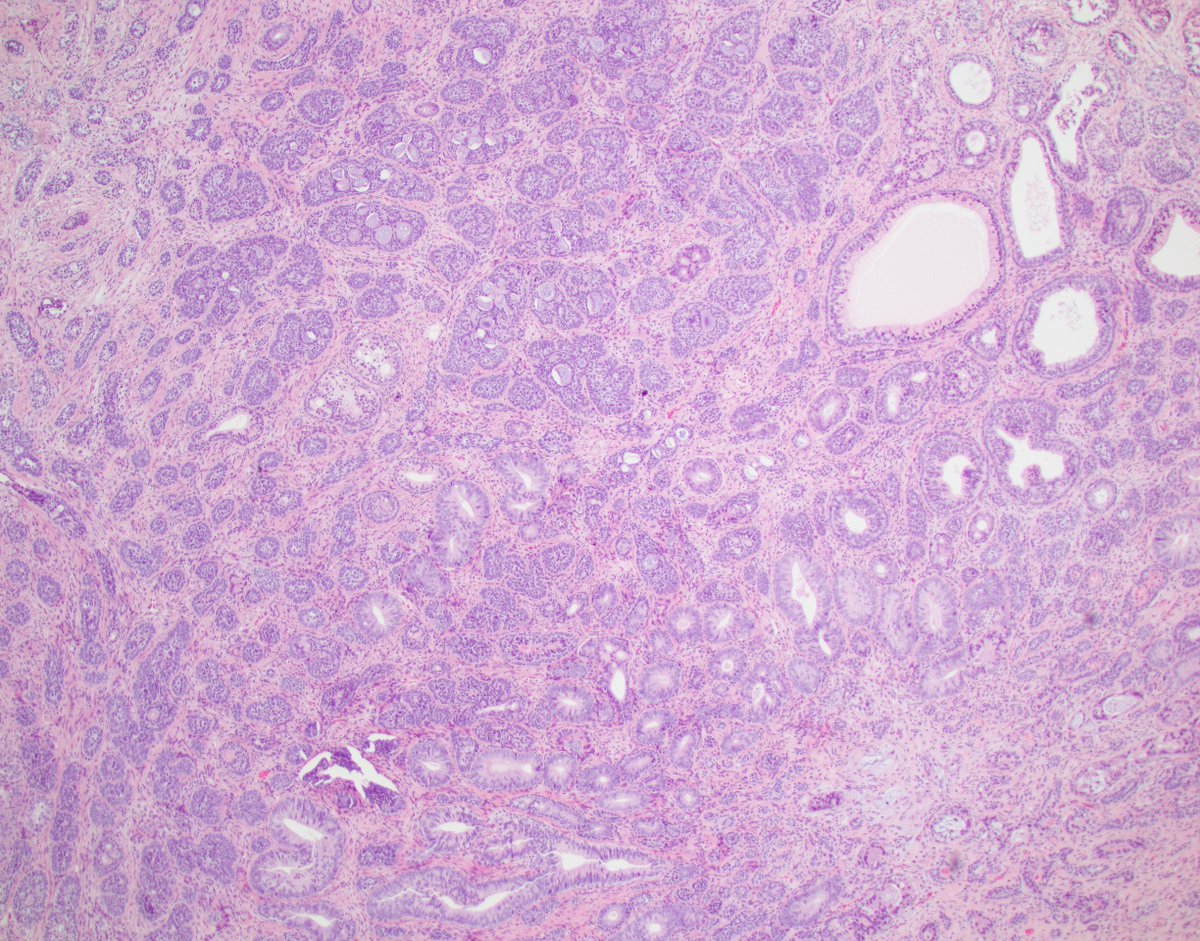

Uro-case. Radical Prostatectomy. A 78 years old man with an Adenocarcinoma Pattern 4 with abundant collagen. #GUpath #Pathres #pathology #PathTwitter #prostate

vintage81106614's tweet image. Uro-case. Radical Prostatectomy. A 78 years old man with an Adenocarcinoma Pattern 4 with abundant collagen. #GUpath #Pathres #pathology #PathTwitter #prostate